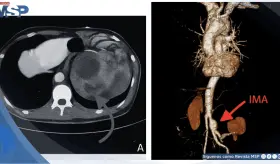

Las imágenes mostraron una aorta abdominal significativamente dilatada, con un diámetro transversal de 4.4 centímetros, muy por encima del límite normal de 3 centímetros.